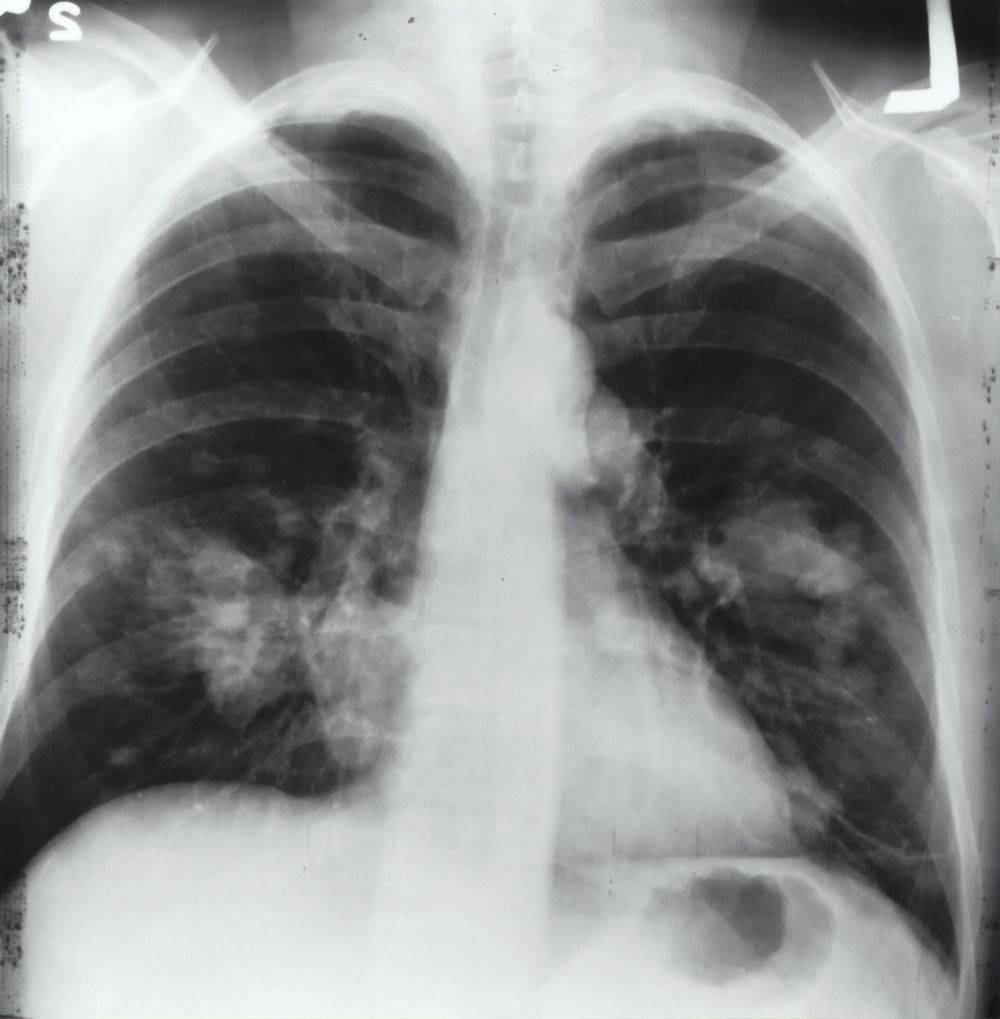

Røntgenundersøgelse